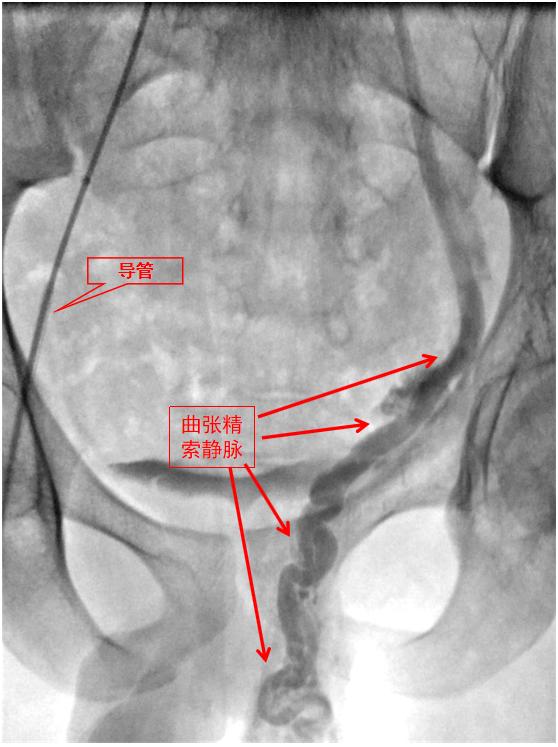

方便与其他治疗方法联合应用,也是介入治疗的优势之一。有些患者因为输卵管病变太严重,无法再通或重建,就只能借助“试管婴儿”等新型助孕方式了。

然而,有些患者输卵管积水严重,病理液体倒流入子宫会引起子宫受孕环境的破坏,试管婴儿也无法着床生长。这时,请介入医生做个“输卵管栓塞术”,就可维持子宫环境的稳定,以保障受孕成功。是不是很神奇?

输卵管栓塞术中,红箭为栓塞物,绿箭为输卵管积水